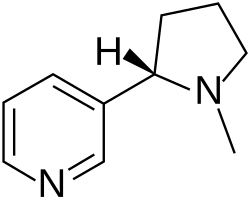

| Active ingredients | Nicotine, harmine |

Tobacco contains the highly addictive stimulant alkaloid nicotine as well as harmala alkaloids.[1] Tobacco use is a cause or risk factor for many deadly diseases, especially those affecting the heart, liver, and lungs,[2] as well as many cancers. In 2008, the World Health Organization named tobacco use as the world's single greatest preventable cause of death.[3]

The addictive alkaloid nicotine is a stimulant, and popularly known as the most characteristic constituent of tobacco. In drug effect preference questionnaires, a rough indicator of addictive potential, nicotine scores almost as highly as opioids.[111] Users typically develop tolerance and dependence.[112][113] Nicotine is known to produce conditioned place preference, a sign of psychological enforcement value.[114] In one medical study, tobacco's overall harm to user and self was determined at three percent below cocaine, and 13 percent above amphetamines, ranking sixth most harmful of the 20 drugs assessed.[115]

Tobacco also contains 2,3,6-Trimethyl-1,4-naphthoquinone (sometimes called 2,3,6-TQ and TMN) which is a reversible monoamine oxidase inhibitor of type A and B with a binding affinity somewhat similar to that of clorgyline and deprenyl. It is a stronger dopamine releasing agent than nicotine and inhibits dopamine metabolism from its MAOI activity.[116][117] Tobacco also contains Harmine and Norharmine which is a reversible MAO-A inhibitor.[118][119][120][121] The MAO-A activity of tobacco alkaloids have been thought to play a role in the addictive qualities of tobacco.[122]